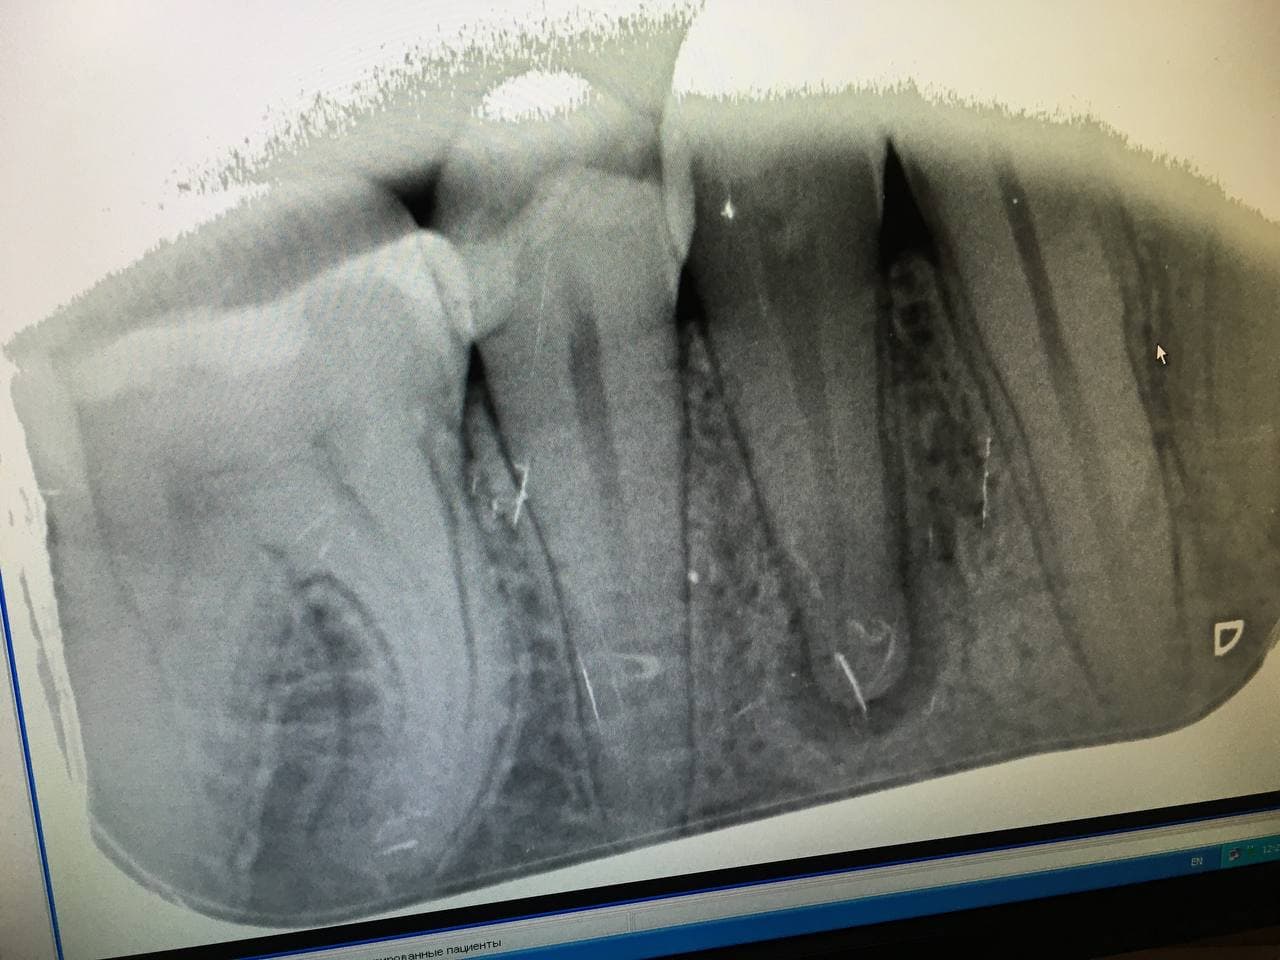

И правильно делают. Восьмерки - атавизм. Примерно как соски у мужчин. Смысла в них мало, вылечить качественно сложно, функции ноль.

Если нет - то нервы дохнут в основном из - за глубокого кариеса, пульпит и периодонтит его осложнения.